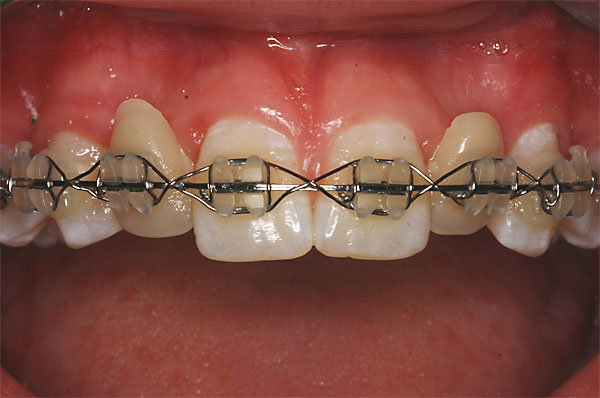

Fall: Von der Prothese zur fixen Krone

1 |

2 |

3 |

|

4 |

5 |

6 |